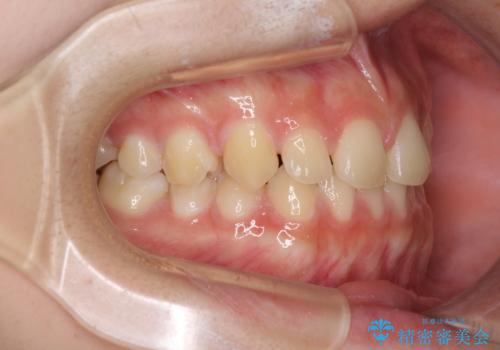

前歯のすきっ歯を治したい インビザラインによる矯正治療

- 上顎前歯の隙間を気にして来院された患者様です。

目立たない装置を希望とのことで、インビザラインを用いて矯正治療を行うこととしました。

一度インビザラインのマウスピースセットをお渡しすると1年以上来院されず、マウスピースを破損したり紛失したりすると来院されるというのんびりとしたペースで治療を行ったため、4年間という長期にわたる治療となりました。

最終的には隙間は全て閉じ、綺麗な仕上がりとなりました。